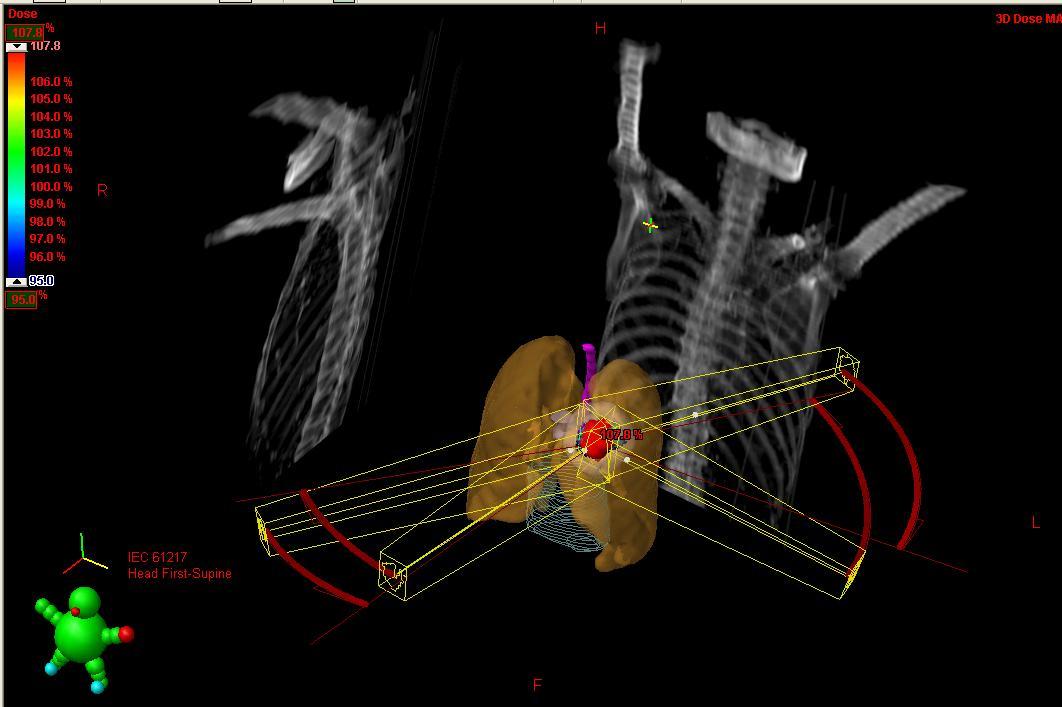

圖一: 全身立體定位放射治療(SBRT/SABR)之3D立體透視圖(紅色為肺部腫瘤)